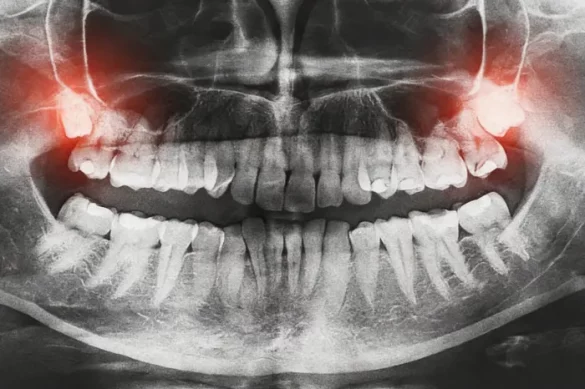

The standard timeline for wisdom teeth eruption is during late adolescence and early adulthood. Most dentists expect wisdom teeth to come in by age 25. This is why dental professionals often recommend X-rays during the teenage years to monitor their growth and decide if removal is needed. When wisdom teeth do erupt, they can cause pain, swelling, and even infections. Some individuals go through this process with minimal discomfort, while others face more severe issues like impaction, crowding, or decay.

If you notice symptoms of wisdom teeth eruption in adulthood, it’s important to consult with a dental professional. Your dentist or oral surgeon will use panoramic X-rays to examine the position and condition of your wisdom teeth. Based on the findings, several management options are available:

The best approach to wisdom teeth—whether they erupt early or late—is prevention and proactive management. Regular dental checkups, even for adults over 30, ensure that hidden or developing wisdom teeth are monitored effectively. panoramic X-rays are especially valuable for locating wisdom teeth before they cause symptoms. Early extraction of problematic teeth can prevent many complications.